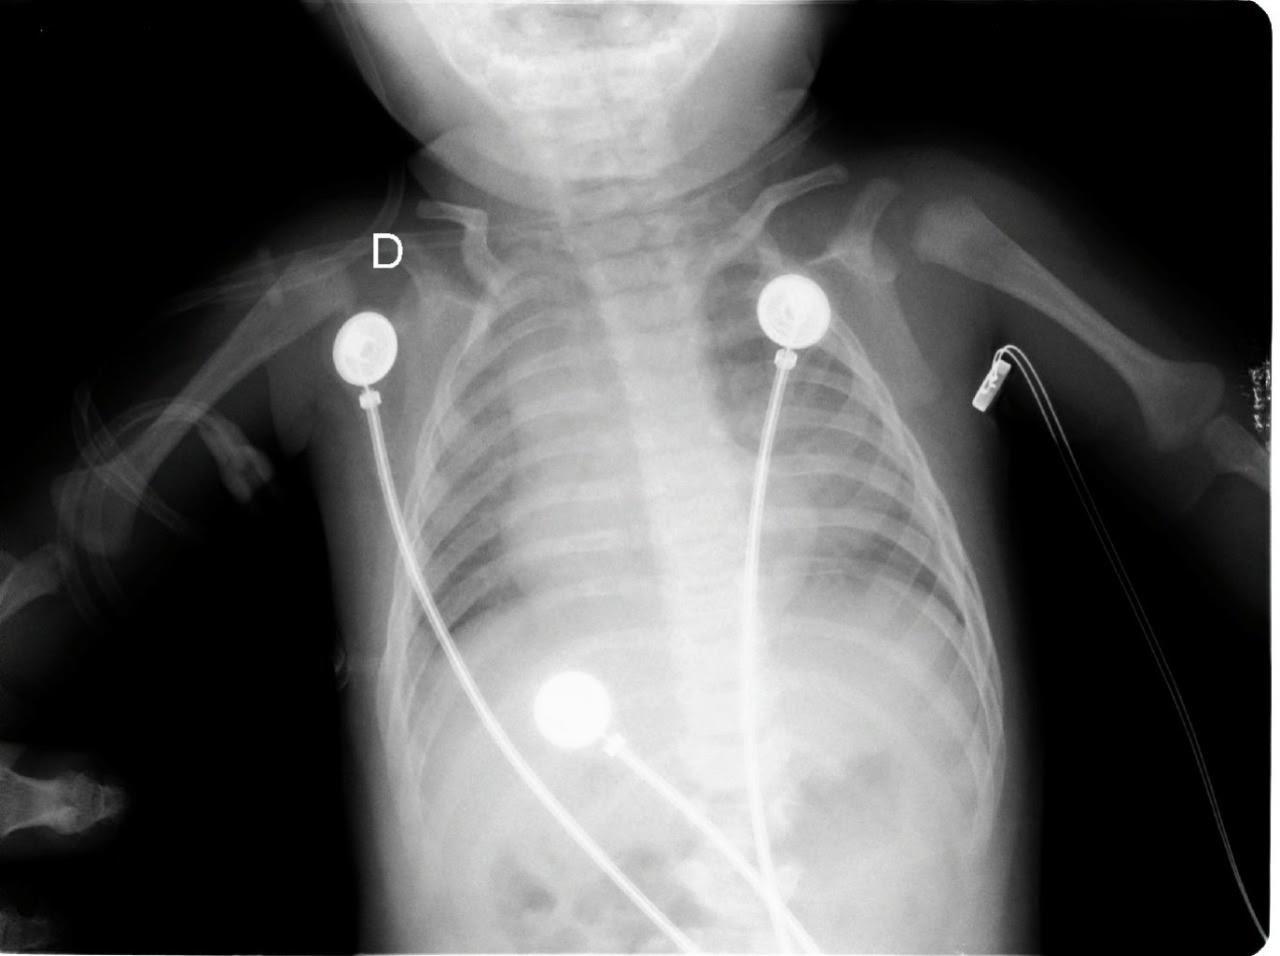

Given these findings, the patient was suspected to be in acute respiratory failure due to severe bronchiolitis. As the patient presented early at the onset of the coronavirus disease 2019 (COVID-19) pandemic, COVID-19 remained high on the differential, given little was known regarding its effects on infants. Oxygen was administered via non-rebreather (NRB) mask with broad spectrum antibiotics and intravenous fluids (IVF) due to concern for sepsis. His labs were notable for white blood cell count of 10.6 x 103 per millimeter (mm3) (reference range: 5x103 - 10x103 mm3) with a lymphocytic predominance; hemoglobin 20.4 grams (g) per deciliter (dL) (14-17 g/dL); creatinine of 0.4 milligrams (mg)/dL (0-0.5 mg/ dL); and a lactate of 12.5 millimoles per liter (mmol/L) (0-4 mmol/L). A COVID-19 polymerase chain reaction test was negative. Chest radiograph was interpreted by the emergency physician as technically limited due to rotation with diffuse prominent interstitial markings concerning for viral pneumonia (Image 1).

Addepalli et al. Point-of-care Ultrasound Diagnosis of Tetralogy of Fallot Causing Cyanosis: A Case Report Image 1. Portable anteroposterior chest radiograph showing no focal infiltrate and limited due to patient rotation.